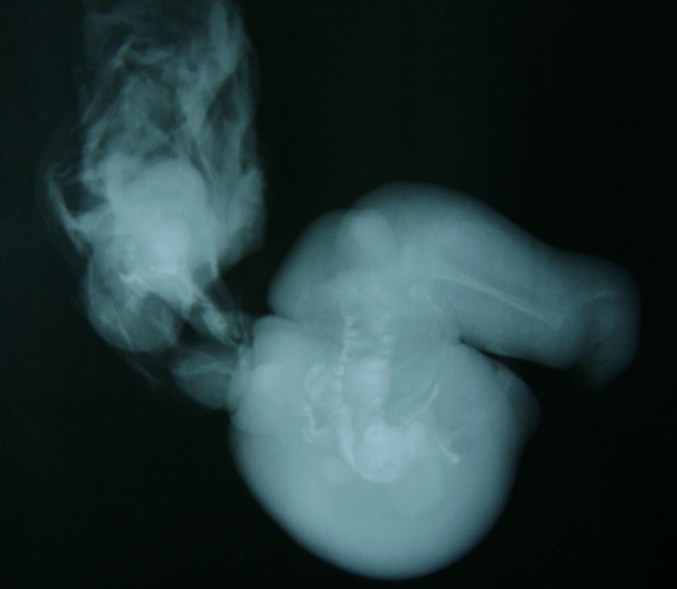

Se pare că băieţelului i se umflase foarte mult burta, iar Radhika şi Hemant, părinţii lui, nu ştiau ce se întâmplă. În urma unei radiografii, medicii au dezlegat misterul. Bebeluşul purta în pântec doi fetuşi. Se pare că indianca avusese tripleţi, dar doi dintre embrioni nu se deazvoltaseră normal. Aceştia fuseseră înglobaţi de cel de-al treilea şi continuaseră să crească în pântecul lui.

Fetuşii au fost îndepărtaţi de medici, iar Durgesh e în afara oricărui pericol.